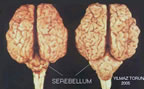

Serebellum-Beyincik

Serebellum

1-Omurgalı beyninin kas koordinasyonunu denetleyen kısmıdır.

2-Beyincik;Loplu bir yapıya sahiptir. Beyincik içindeki ak madde bir ağaç gibi boz madde içinde dağıldığı için bu kısma hayat ağacı denir.

Beyincik, vücuttaki kas faaliyetini düzenleyerek, vücudun dengeli hareketini sağlar. Beyinciği çıkartılan bir kuş dengesiz bir şekilde uçmaya çalışır.